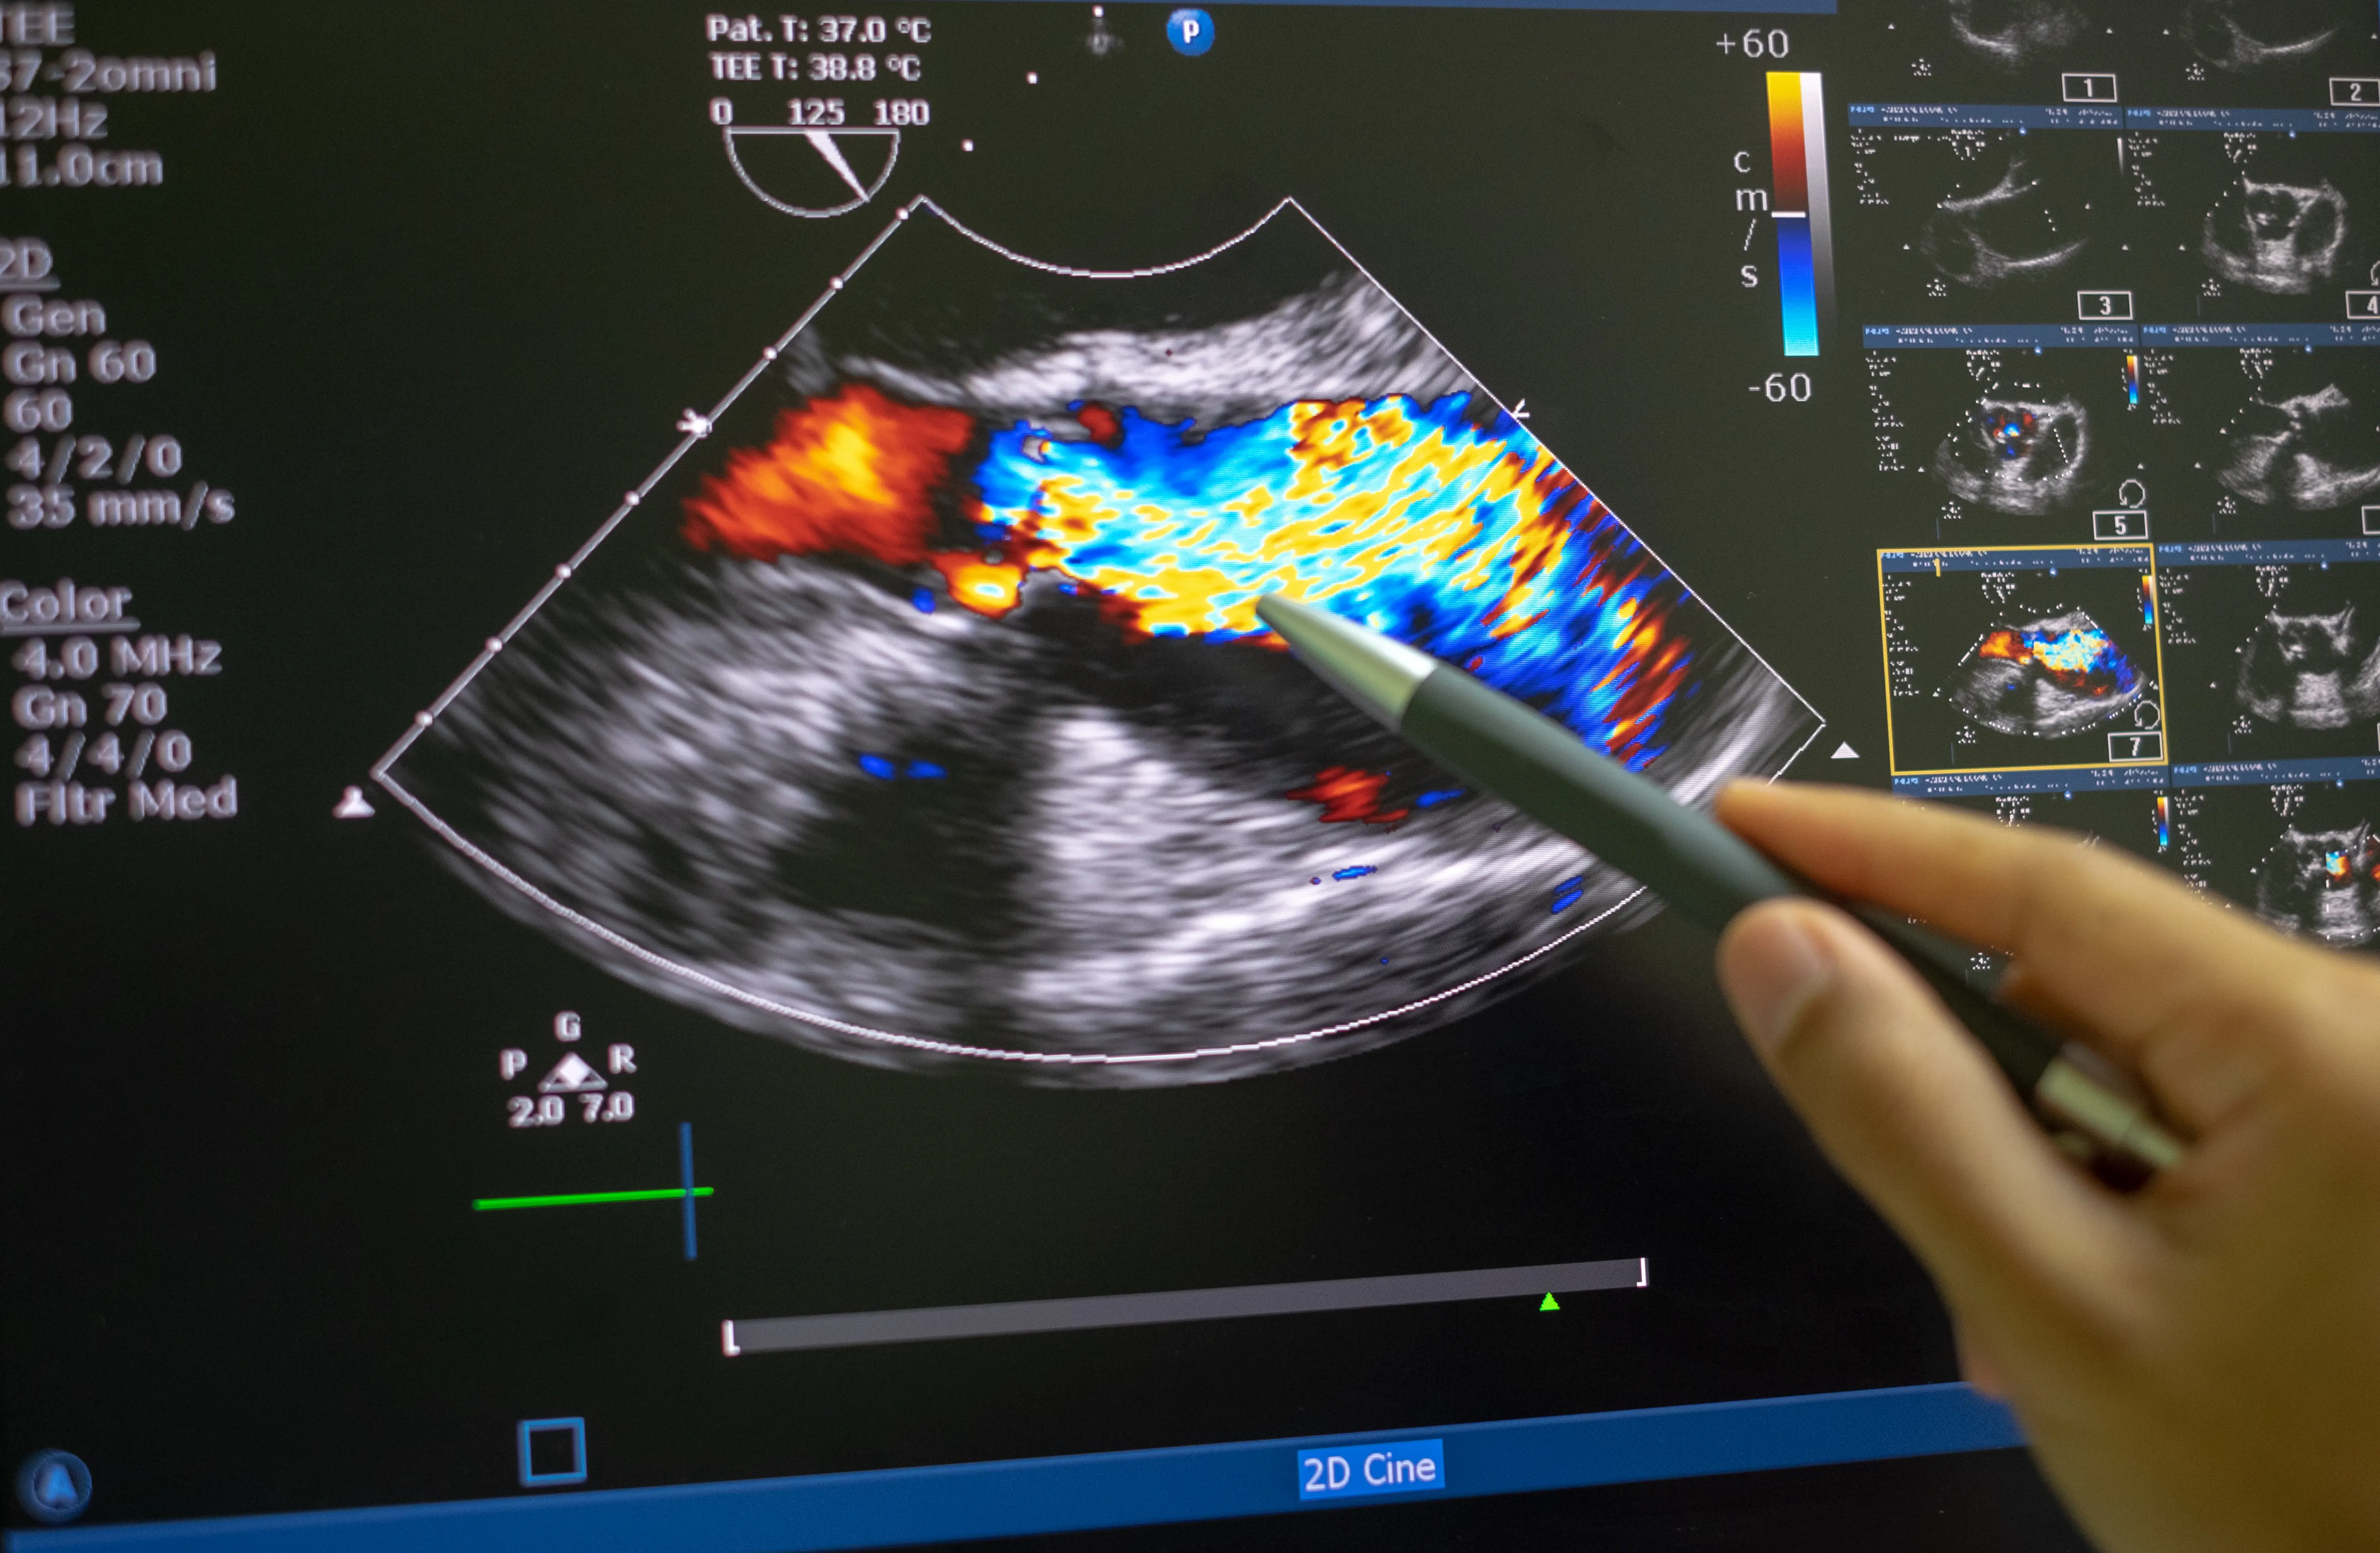

Kalp Kapak Hastalıkları: Teşhis ve Tedavi Yöntemleri

Kalp Kapak Hastalıkları: türleri, belirtileri, teşhis (EKO, EKG) ve ilaç, girişimsel ile cerrahi tedavi seçeneklerini kapsamlıca öğrenin.